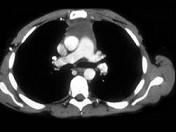

问题 男,64岁,胸部隐痛伴眼睑下垂2月余,请结合影像学检查,选出最可能的诊断 ( )

选项 A.淋巴瘤 B.胸腺瘤 C.胸内甲状腺肿 D.纵隔畸胎瘤 E.间皮囊肿

答案 B